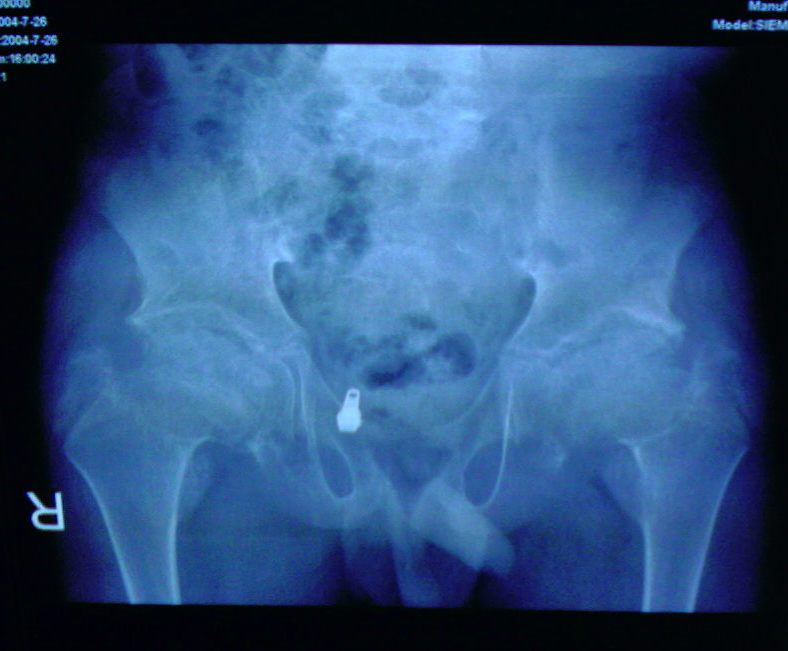

征像:片子的质量也太寒碜了点,也来知道是不是同一个病人的,故且将其当做一个病人分晰下吧。患者男性,年龄应该在10到16岁左右。胸段脊柱明显后突,腰段脊柱明显前突,部分椎体有鸟嘴状改变?髂骨较窄,坐骨大切迹小,髂骨体明显肥大,髋臼缘增生硬化,毛糙,股骨头骨化中心稍有变平,边缘毛糙且密度不均匀,股骨颈粗短,有髋内翻改变。肱骨中段较粗,向下至干骺端变小,肘部各骨骺骨化中心肥大畸形,上尺桡关节对合不良。膝关节骨骺骨化中心肥大畸形,且发育不对称,以股骨内髁为著,胫骨平台骨性关节面稍有硬化,不平整。膝关节有外鄱改变,肘膝部先期钙化带均有密度增高。

意见:考虑原发或者继发的以骺板软骨及关节软骨发育生长异常为主的骨发育生长异常。(个人考虑的病有1大骨节病2粘多糖贮积症及相似病变如脊柱骨骺发育不良及粘脂贮积症3血友病)